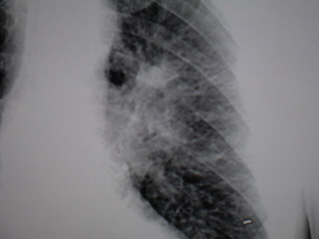

Иллюстрации 8. Томограмма в срезе 7 см. На фрагменте томограммы с увеличением изображения тень корня раздельно и структурно не дифференцируется.  «Линейные» компоненты от корня направлены латерально и краниально. Структура затемнения    неоднородная, с мелкими просветлениями. Наружный контур «затемнения» не ровный, не чёткий.

8. Томограмма.

8. Фрагмент томограммы.